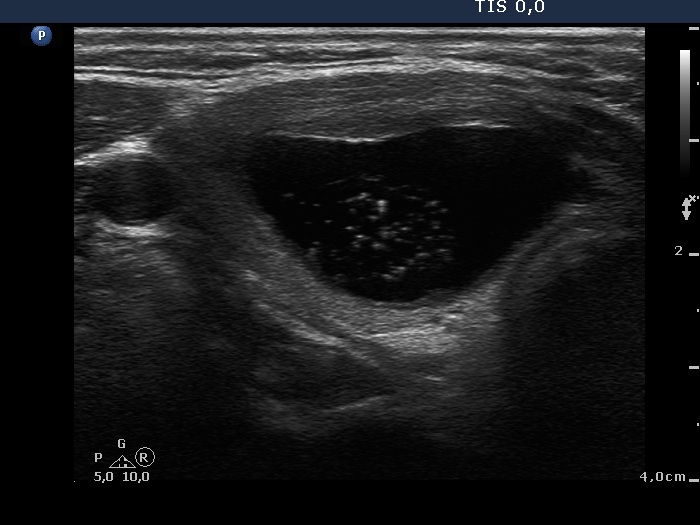

Benign colloid goiter (cytological diagnosis) - case 386 |

At first sight, this pattern mimics the starry sky phenomenon which would be caused by numerous microcalcifications. However, these granules are found in a cystic fluid therefore they cannot be punctate echogenic foci (microcalcifications).